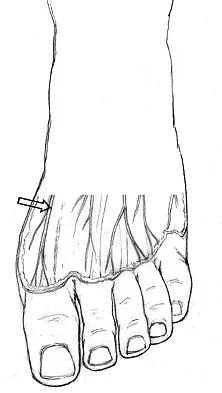

The dorsal digital cutaneous nerve of the great toe shown in Figure 8 is a branch of what nerve?